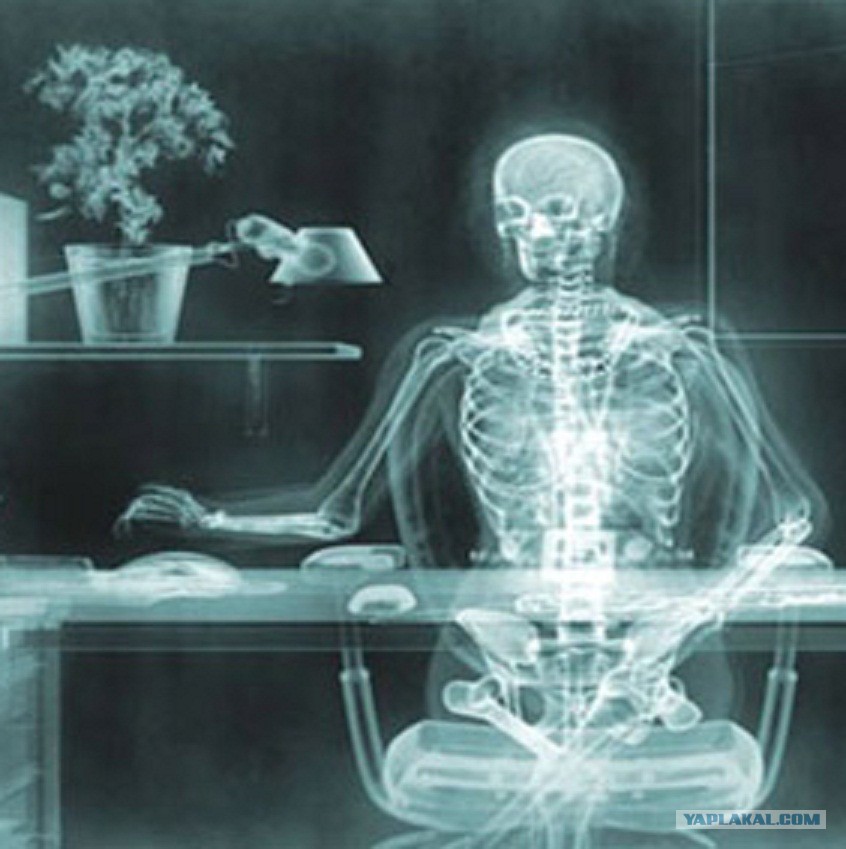

Рентгеновские снимки плат в высоком разрешении

Раздел: Точки зрения